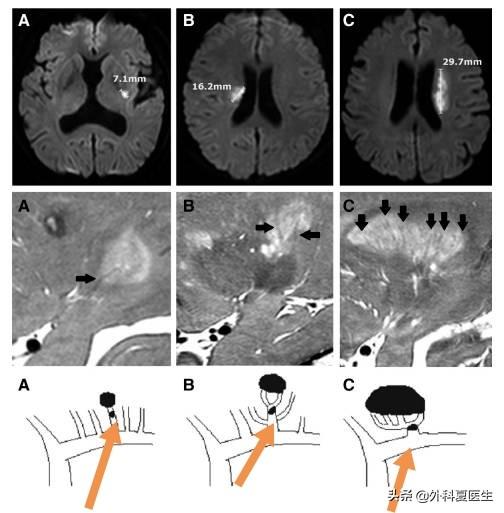

まず、詰まる脳血管が比較的小さく、梗塞領域も比較的小さい。梗塞は通常100ミクロンの血管に発生し、梗塞面積、すなわち病変の大きさは通常1cm以下である。

第二に、ラクナ脳梗塞の部位はより明確であるのに対し、脳梗塞の一般的な部位は不確定である。海綿状梗塞は、主に脳内の穿通動脈(中動脈、後動脈、脳底動脈など)に発生します。したがって、海綿状梗塞の発生部位は、通常、脳の大脳基底核領域、視床、脳橋などである。